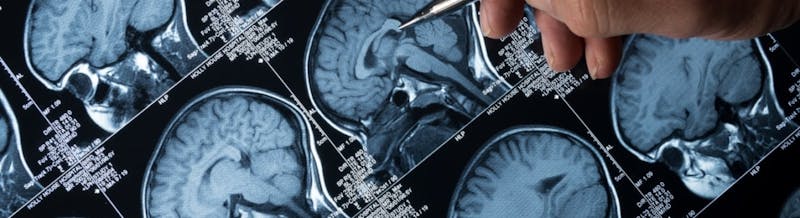

ब्रेन ट्यूमर के कारण होने वाले लक्षण बच्चे की उम्र के साथ अलग-अलग होते हैं, लेकिन इसमें सिर की परिधि का बढ़ना, सिरदर्द, मतली और उल्टी, दौरे, पहले से प्राप्त मोटर कौशल जैसे चलने में नई शुरुआत में कठिनाई शामिल हो सकती है। बच्चे अक्सर वयस्कों की तुलना में चिकित्सा के लिए देर से आते हैं क्योंकि वे अपने लक्षणों से इनकार कर सकते हैं और गंभीर लक्षण पहचाने नहीं जा सकते हैं। बाल चिकित्सा ब्रेन ट्यूमर का निदान आमतौर पर मस्तिष्क की सीटी और/या एमआरआई इमेजिंग से किया जाता है।